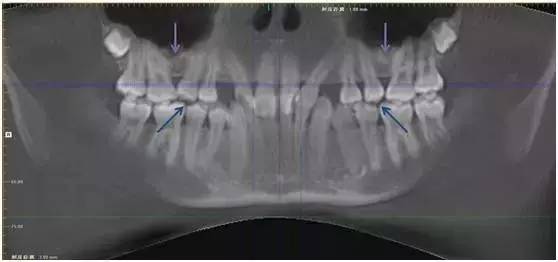

这种情况即使进行正畸治疗,也会因为局部骨量不够,出现第二双尖牙无法牵引到位或根周骨量不够的风险。

因此患者接受了上颌窦底提升植骨术,一年后牙槽基骨成骨充分,牙齿自行正位萌出。此时再进行正畸治疗,难度和风险将大大减小。

图:上颌窦底提升植骨术后一年